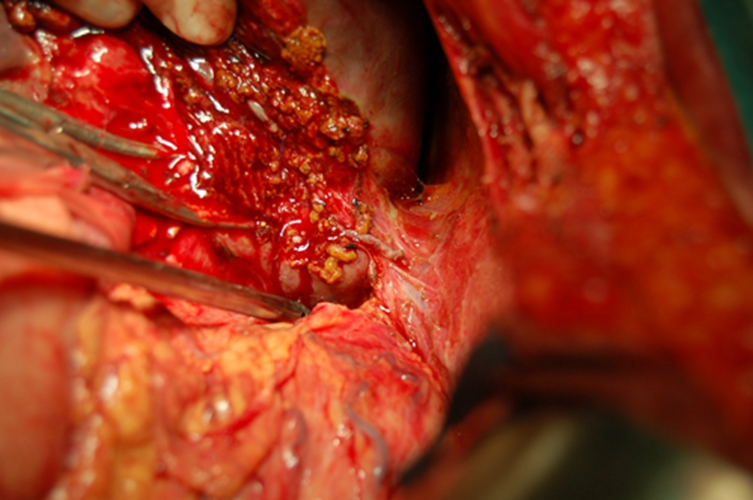

膽管癌圖片

總膽管癌晚期

下段膽管癌

小細胞膽管癌

早期肝膽管癌

上段膽管癌